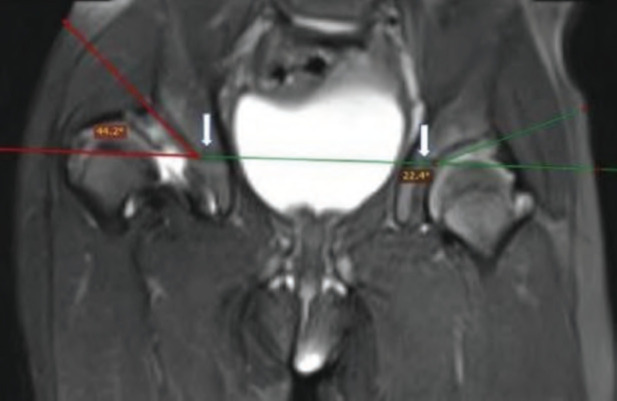

Material and methods: A prospective cohort study was conducted in unilateral idiopathic DDH cases those who underwent an open reduction in the age group of one to four years. Pre- and post-operative MRI was done to assess various acetabular and femoral parameters. Intra-operatively, osteotomy was planned. Based on stability assessment given by Zadeh et al Clinical follow-up assessment was done at three- and six-month post-op. Functional assessment using Modified McKay's criteria was done at six months follow-up.

Results: Out of 15 cases, seven children underwent only open reduction (OR), whereas eight underwent OR with Salter's osteotomy. Based on pre-op acetabular index and anteversion, Salter's osteotomy should be done in 14 out of 15 cases, but intra-operative stability test precluded Salter's in 6 cases. Post-operative anterior sectoral angle and femoral head coverage percentage were better in OR with Salter's group than OR-only group, but not statistically significant. Functional assessment at final follow-up showed all OR with Salter's group cases were Grade I, whereas in OR-only group, 4 were Grade I and 3 were Grade II.